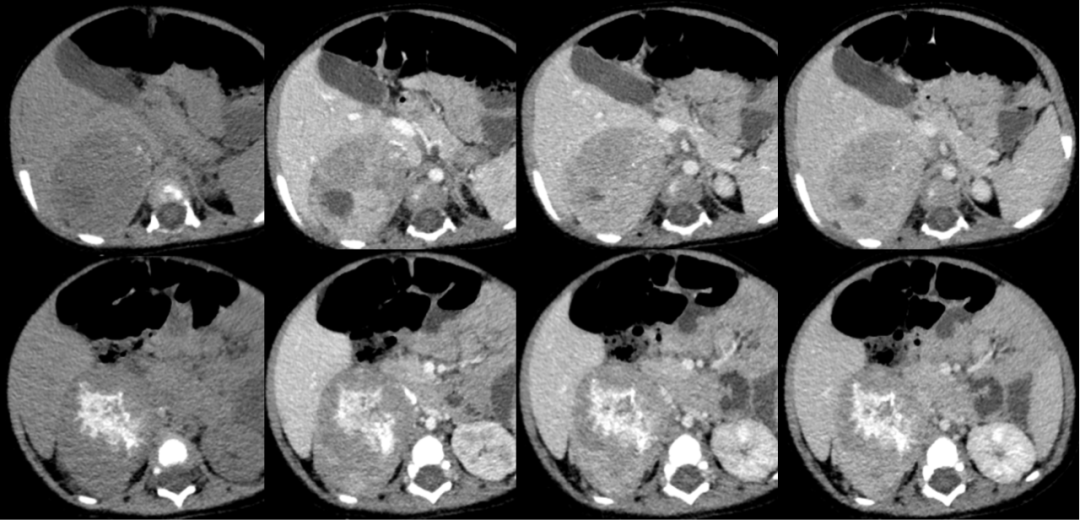

病例二

男,9 岁,因「腹泻、呕吐 2 天,发现腹腔肿物 1 天入院」。

影像描述:右侧肾上腺区见团块样高低混杂密度影,平扫其内见钙化影,大小约 6.6 cm,增强扫描不均匀强化。